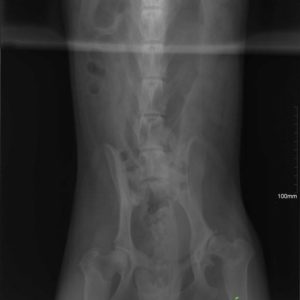

Vielen Dank an Alexander Englert, dass er möglich gemacht hat für Mex , seine Hüft- Dysplasie – Operation zu finanzieren. 🙂 Noch zweieinhalb Monate Rehabilitation und wir können eine neue Familie suchen für Mex! 🙂 Kategorie: NewsVon Csillag Alexandra2017-09-14 Share this post Share on FacebookShare on Facebook Share on XShare on X Autor: Csillag Alexandra http://www.ebarvahaz.hu KommentarnavigationZurückVorheriger Beitrag:Lola – Eine kleine wunder!NächstesNächster Beitrag:Vielen Dank Mirabella Hesz für die Spenden!Related postsTamara und ihre 7 kleinen Babys2026-01-13Hallo Mangó!2026-01-09Hallo unsere Lieben!2026-01-08Unsere neuesten Bewohner sind angekommen!2025-07-11Bözse <32025-04-10Überraschung2025-01-29